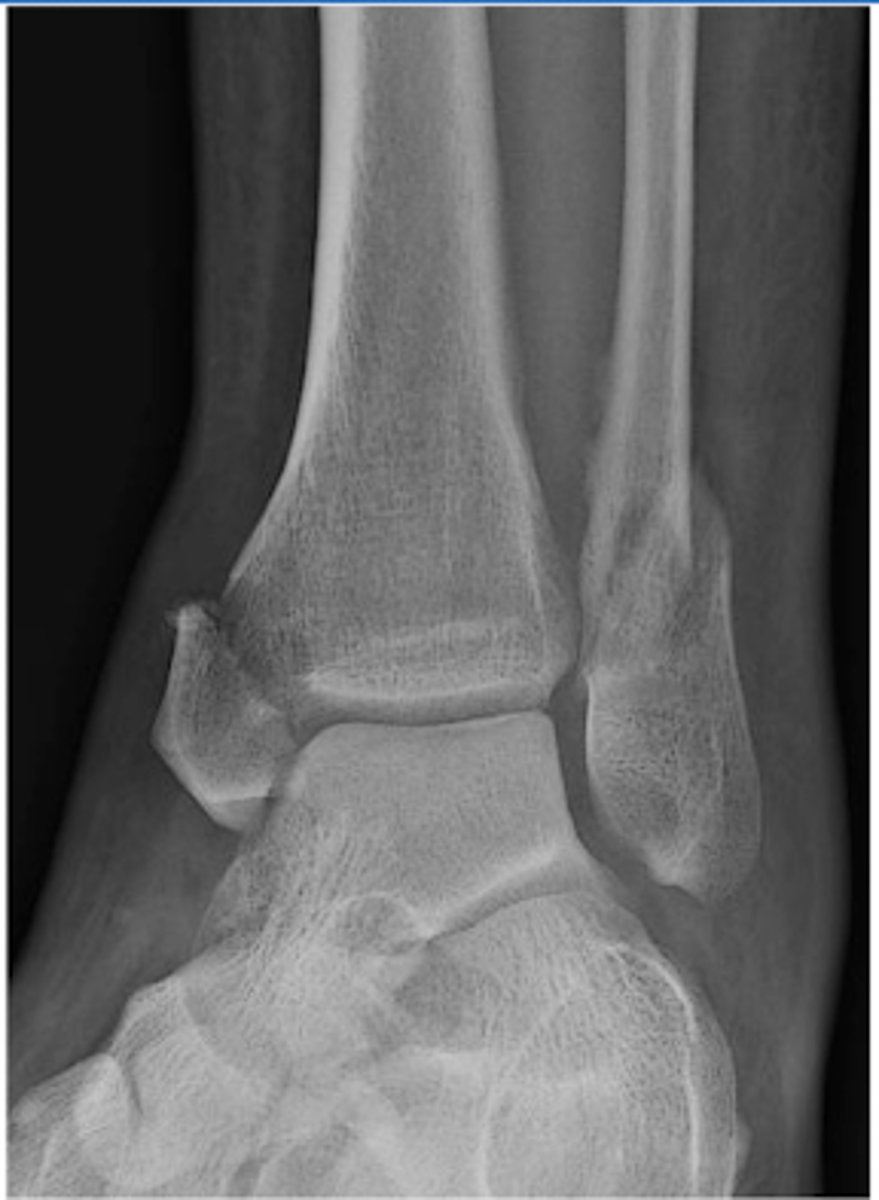

What is a bimalleolar ankle fracture?

involves BOTH the medial and lateral malleolus

What is a trimalleolar ankle fracture?

involves all THREE malleoli - medial, lateral and